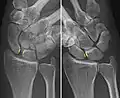

Dynamic scapholunate instability visible upon clenching the wrist

Xray indicates scapholunate ligament instability when the scapholunate distance is more than 3 mm, which is called scapholunate dissociation.[7] A static instability is generally readily visible, but a dynamic scapholunate instability can only be seen radiographically in certain wrist positions or under certain loading conditions, such as when clenching the wrist, or loading the wrist in ulnar deviation.[6]

In order to diagnose a SLAC wrist you need a posterior anterior (PA) view X-ray, a lateral view X-ray and a fist view X-ray.[8] The fist X-ray is often made if there is no convincing Terry Thomas sign. A fist X-ray of a scapholunate ligament rupture will show a descending capitate. Making a fist will give pressure at the capitate, which will descend if there is a rupture in the scapholunate ligament.